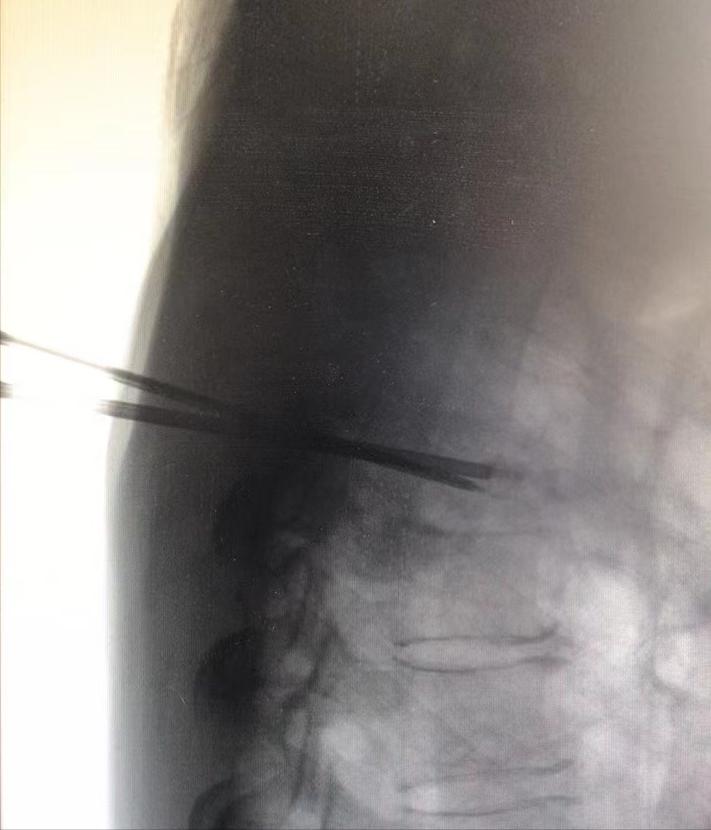

双侧入路成功置针至靶点后,首先进行单针35W、靶温度60℃射频消融椎体肿瘤10分钟。

单针射频消融椎体肿瘤(侧位)